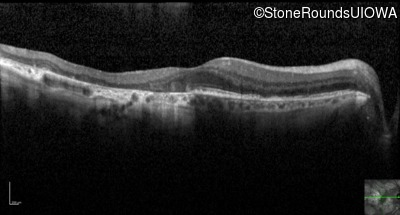

Optical Coherence Tomography - Right - 20/40 -2

Exemplar / OCT Stack

Optical Coherence Tomography - Left - 20/40 +1